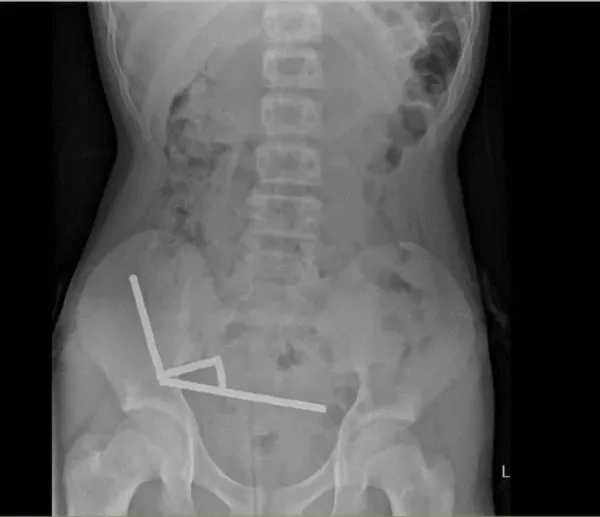

医生通过 X 光片观察到,男孩肠道的不同部位出现了四条线状的磁铁链。

腹部 X 光片显示了磁铁分布情况 来源:Lekamalage et al.,?NZMJ, 2025

200 颗磁铁在患儿腹中形成了磁铁链。来源:Lekamalage et al.,?NZMJ, 2025